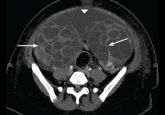

ArticleOvarian hyperstimulation syndrome as a complication of molar pregnancyAuthor:Gerald Behr, MDPublish date: July 1, 2016An 18-year-old woman, 14 weeks pregnant, presented with bleeding, cramping, and a fundal height of 23 cm.Read More